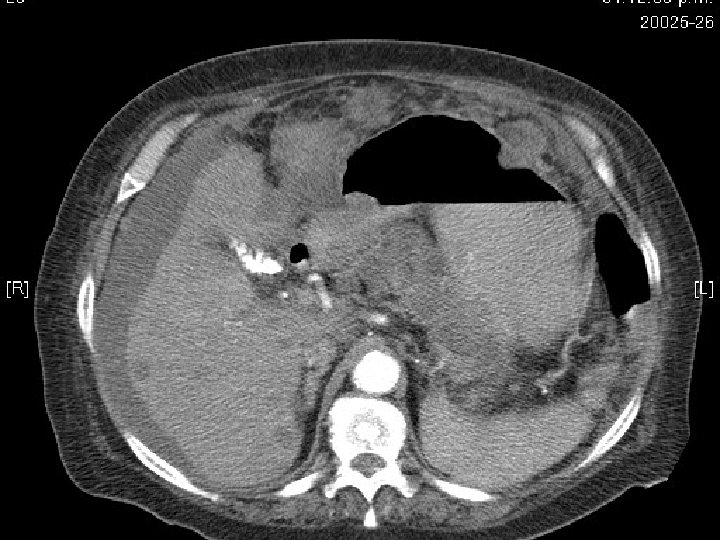

Tomografía abdominal • Hígado con presencia de nódulo de 10 mm en el segmento 3. • Estómago distendido con abundante contenido liquido en el fondo con paredes gruesas a nivel del antro de 12 mm que condicionan estrechez de la luz, infiltran duodeno. • Infiltración de la grasa perigástrica que infiltra páncreas. No se definen adenopatías adyacentes. • CC: quiste hepático. NM gástrico con infiltración a páncreas y grasa perigástrica, cabeza de páncreas prominente.

Cáncer Avanzado Lesión Fungosa

TAC y Cáncer Gástrico • Para la metástasis linfáticas, la sensibilidad de la TC varía de 48% a 91% La sensibilidad de la TC en la detección de un metástasis a distancia es del 57%. Por último, se reconoce generalmente que la TC es pobre en la visualización de pequeños nódulos peritoneales, excepto en la presencia de ascitis. En general, la TC tiende a disminuir el grado de cáncer gástrico y puede ser más útil en la identificación de enfermedad en estadio avanzado. • El 25% de los ganglios metastásicos medida de 5 mm de o menos y no detectable por la mayoría de las técnicas de imagen. Andaker L, Morales O, Hojer H, et al. Evaluation of pre-operative computed tomograghy in gastric malignancy. Surgery 1991; 109: 132.

TAC: signos tomográficos